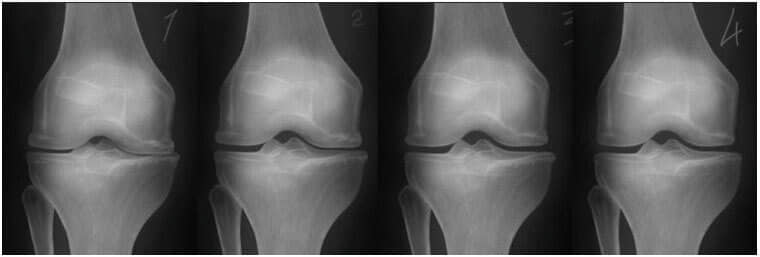

И тогаш се случило чудо. Овој лекар почнал секој ден да оди во домот на Виолета и ја мачкал со овој лековит гел. Четири недели подоцна, таа успеала да стане од нејзината инвалидска количка и сама да оди на лекар. По шест недели, зглобовите на Виолета Јовановска целосно заздравеле од остеоартритис. Рендгенскиот тест го потврдил тоа.

Одлево: рендгенската снимка на десното колено на Виолетова Јовановска, 75 години. Ткивото на 'рскавицата е речиси целосно уништено. Препорака на лекарите е зглобот да го замени со вештачки.

Оддесно: рендгенската снимка на десното колено на Виолета Јовановска после лекувањето со гелот Nautobone.

– Рендгенските снимки подолу ја покажуваат типичната слика за заздравувањето на зглобот на коленото.